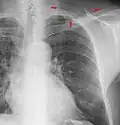

A normal posteroanterior (PA) chest radiograph of someone without any signs of injury. Dx and Sin stand for "right" and "left" respectively.